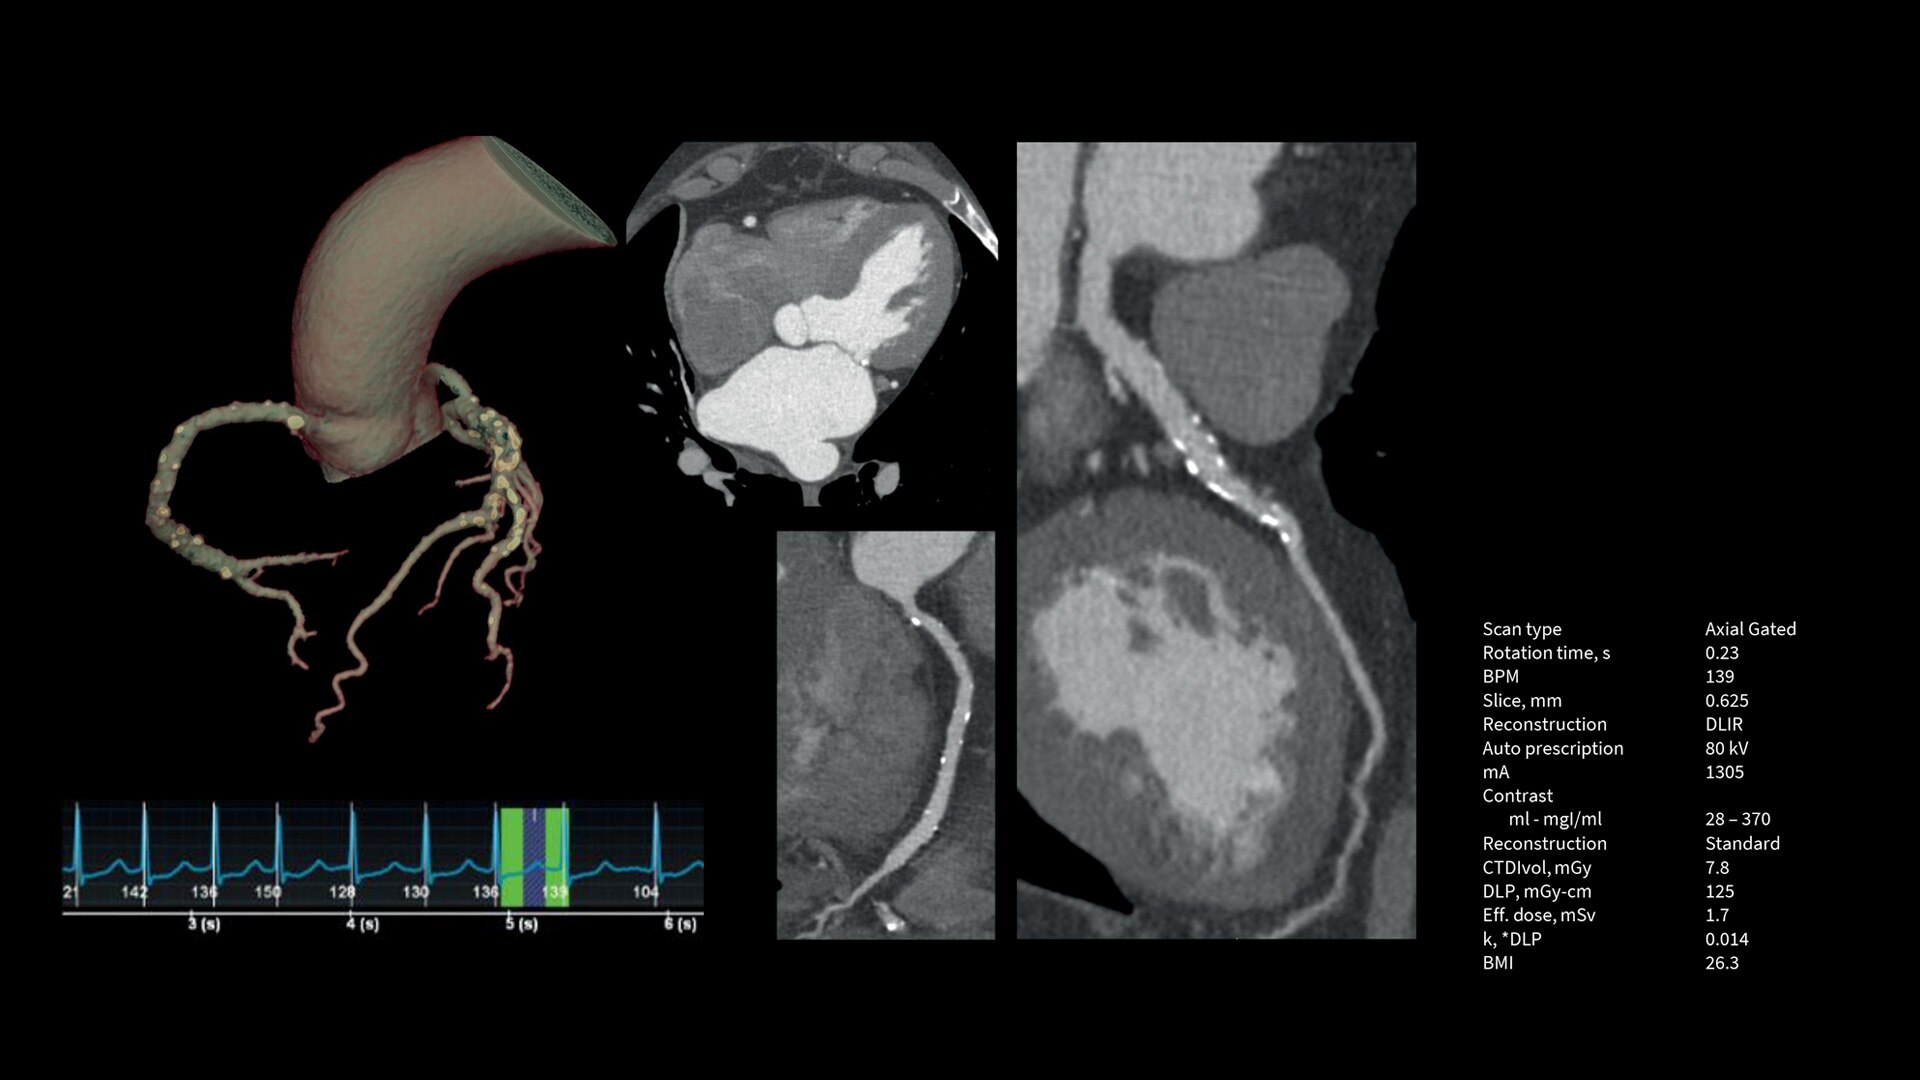

Upgrade to the industry's fastest rotation time

The Revolution Apex platform allows you to upgrade your gantry rotation speed. You can start with 0.28 sec gantry rotation time, and at any point in time when you need to advance your cardiac capability, you can upgrade to 0.23 seconds per rotation with the industry’s fastest rotation time.